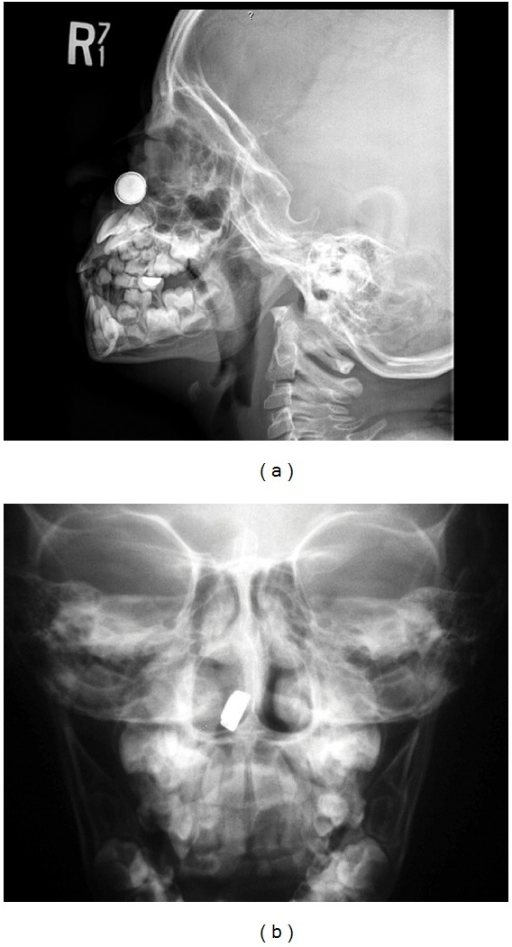

From www.researchgate.net

The button battery ingested by the patient. These battery changes Button Battery Wikem If foreign body is button battery or multiple magnets (especially strong rare earth magnets), requires immediate removal in ed. If battery is beyond reach of endoscope, surgical removal is reserved for unusual patients with: This guideline has been written to cover the uncommon presentation of button battery or multiple magnet ingestion in a child. Call the national button battery ingestion. Button Battery Wikem.